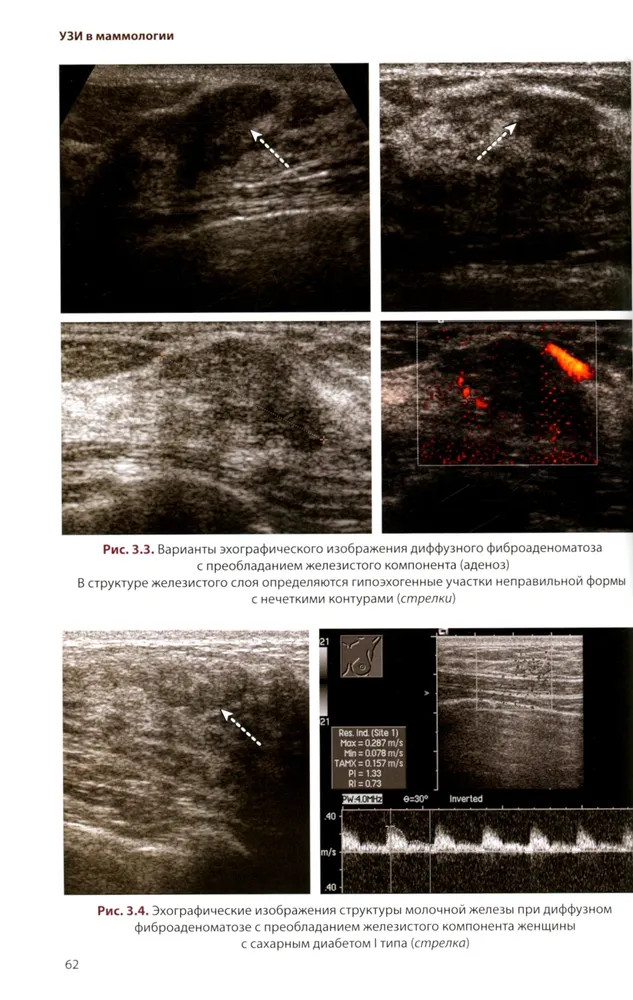

💳 Оплатить за товар можно при получении 🇰🇿 Есть бесплатная доставка по Казахстану от 1 дня 🎁 Копите бонусы с каждой покупки Руководство посвящено изучению возможностей различных методик УЗИ в диагностике доброкачественных и злокачественных опухолей молочных желез, доброкачественных процессов и воспалительных заболеваний. На основе анализа литературных данных рассматриваются вопросы этиологии, морфологии и классификации опухолей молочных желез. Отдельная глава посвящена методике и нормальной ультразвуковой анатомии молочных желез. Подробно изложены семиотика опухолей молочных желез, а также вопросы применения УЗИ в определении стадии опухолевого процесса согласно классификации TNM. Для специалистов по лучевой диагностике, а также врачей других специальностей в области маммологии. Руководство может быть рекомендовано для подготовки в системе последипломного непрерывного профессионального образования. |